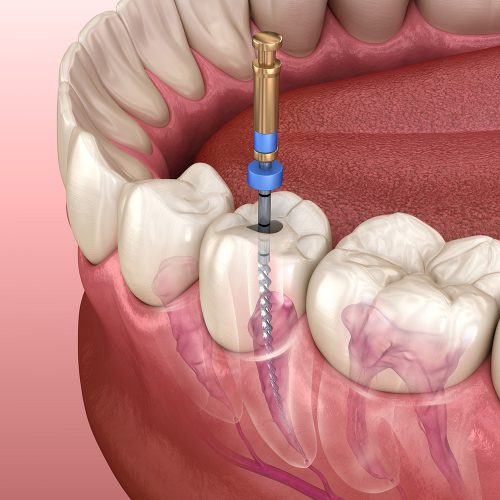

If you have extensive decay, and the infection has reached the pulp area of the tooth, a root canal may be needed. Both fillings and root canals are great ways to save teeth, and prevent further decay or infection. We always choose the best treatment option depending on the condition of the tooth.

If the decay is extensive and the infection has reached the pulp of the tooth, a root canal may be required. If a tooth is broken or cracked and not treated, it may become infected, necessitating root canal therapy. The diseased pulp is cleansed and sealed during root canal therapy to heal the tooth. A dental crown may be applied to entirely restore the tooth’s functionality if it is required.